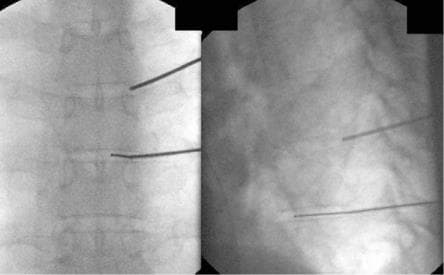

Нами розроблена методика, що дозволяє успішно проходити голкою в потрібний міжхребцевий диск і проводити в центр його лазерний промінь. Дія лазерного променя така ж, як і при лікуванні шийних або поперекових дисків.

- У найбільш складних випадках ми можемо проводити операцію не тільки під контролем рентгенапарата, а й під контролем комп'ютерного томографа

- Операція проводиться під місцевим знеболенням

- Операція триває близько 30 хвилин

- Якщо операція проводиться під комп'ютерним томографом, операція може тривати до 45 хвилин